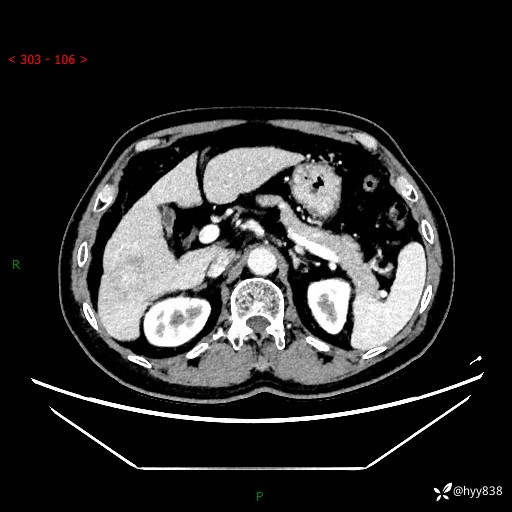

增强动脉期